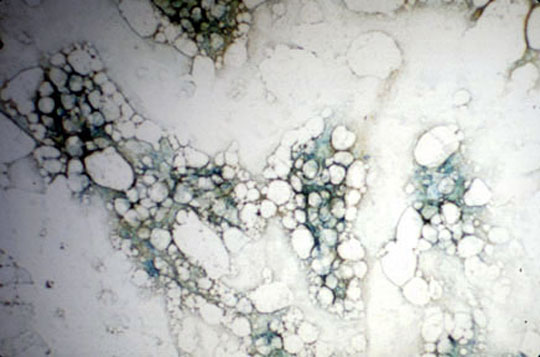

- Reticulocytes with polyribosomal remnants (RNA) staining dark in their cytoplasm. They are slightly larger than the completely mature

erythrocytes and are often found in the peripheral bloodstream at times when blood

cells are being formed unusually rapidly (as during or after certain blood diseases).

- Reticulocytes in the blood in hemolytic anemia

Dr Harry Messmore